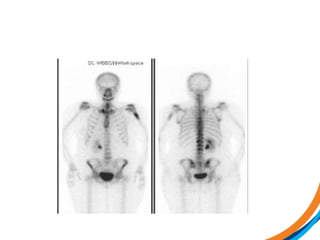

Case study 3(Patient 009) • 44, Female, ECOG 1 • RCC diagnosed 2007. Metastatic recurrence in 2012 • Prior RT to prevascular LN 50Gy/20# (2012) • Started on Pazopanib, then everolimus • Recent MRI spine shows met involving T3 and L1 vertebral body, with involvement of superior endplate (L1)  1) Review the images  2) Target the lesion

• 40.

• 41.